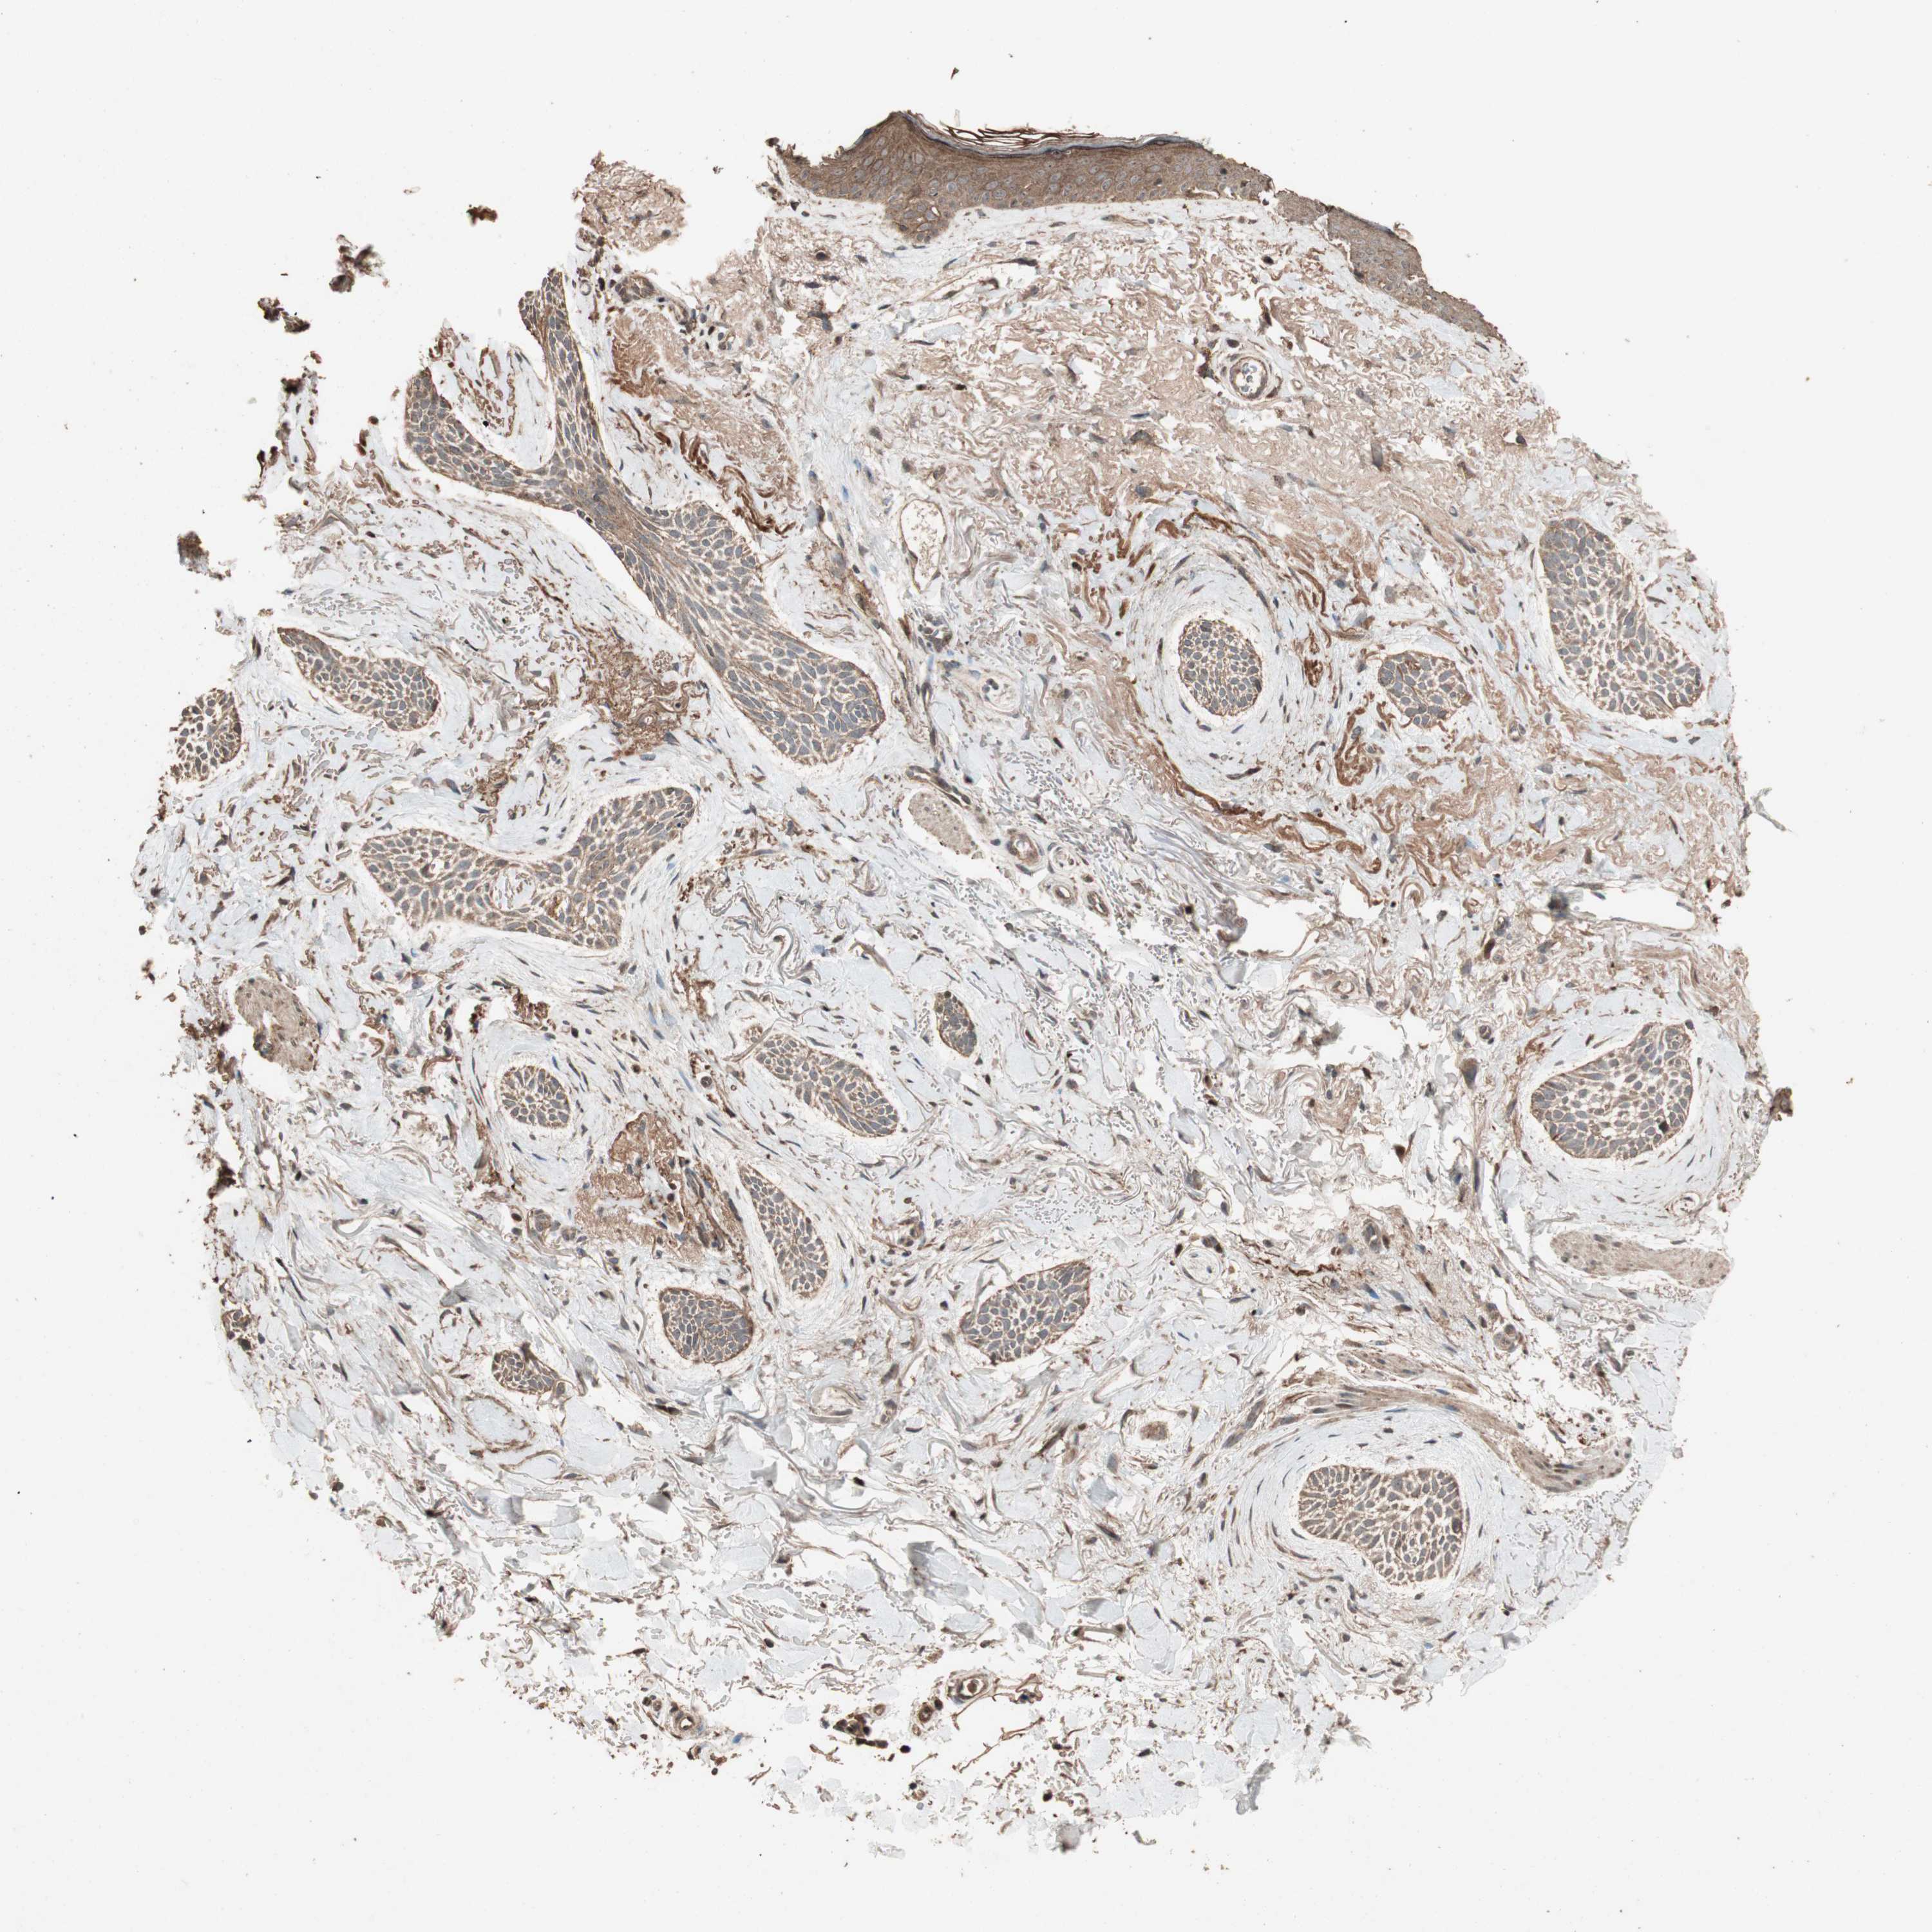

SKIN CANCER - Protein expressioni

A mouse-over function shows sample information and annotation data. Click on an image to view it in a full screen mode. Samples can be filtered based on level of antibody staining by selecting one or several of the following categories: high, medium, low and not detected. The assay and annotation is described here.

Each image is clickable and will lead to virtual microscopy that enables deeper exploration of all samples and also displays staining intensity scores, fraction scores and subcellular localization as well as patient and tissue information for each sample.

Antibody HPA006287

Staining

Low

Intensity

Weak

Quantity

<25%

Location

Cytoplasmic/membranous

Squamous cell carcinoma, metastatic, NOS